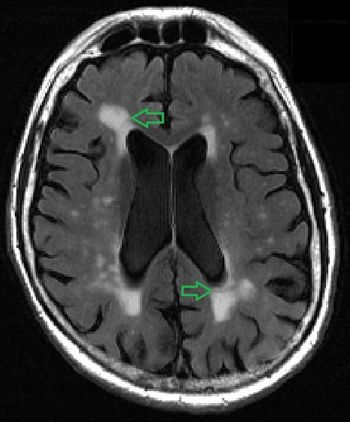

A tool that objectively measures the volume of white matter lesions can accurately pinpoint evidence of early dementia.